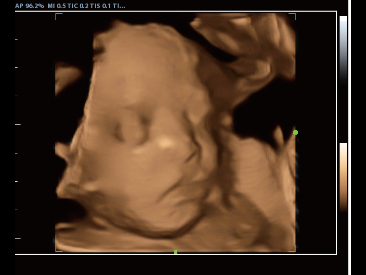

• dp-50-exp-fig6-6

3D 胎儿面部